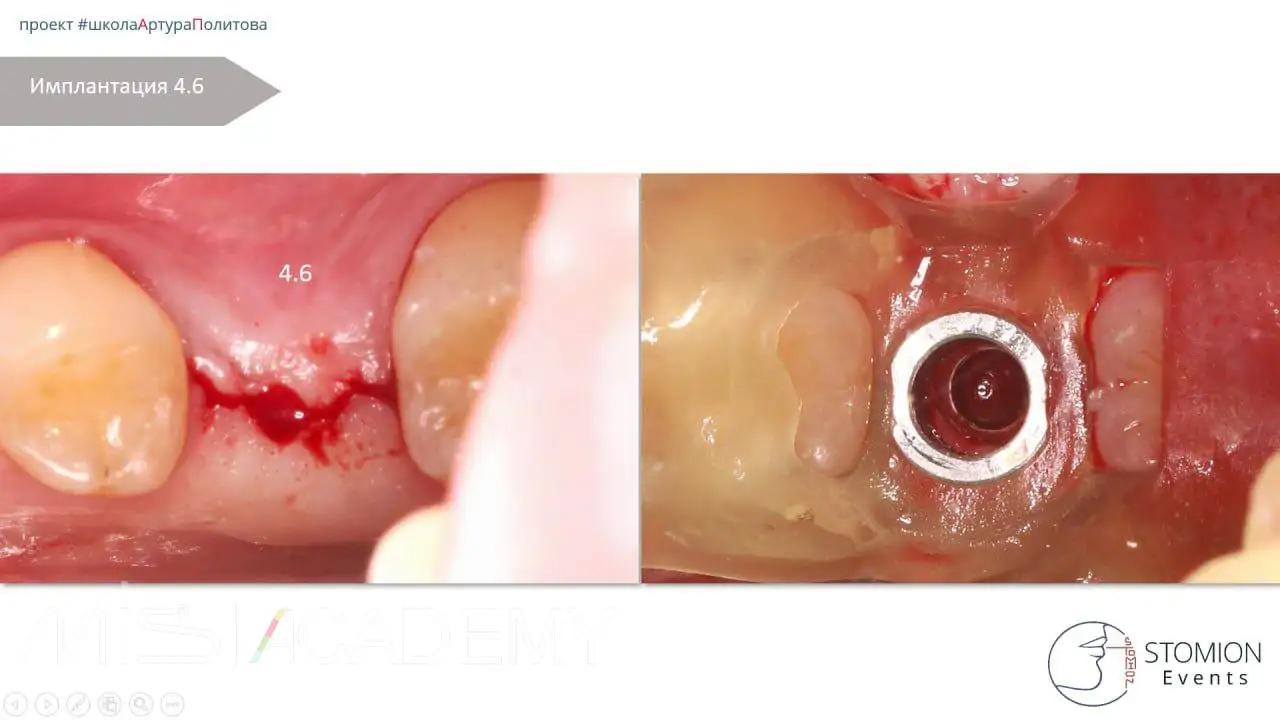

Имплантация MiS C1, 1.6 + ЗСЛ, 4.6.

— 4.6 — торк 15 Н/см, ввиду кости D4, установлена высокая (3мм) заглушка.

— Раскрытие через 4 месяца.